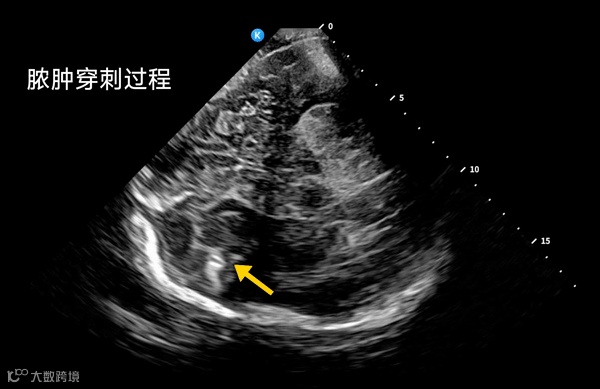

在2025年重庆市卒中学会第七届年会暨西部脑血管联盟大会上,清华大学附属北京清华长庚医院张华斌教授指出,未来颅脑超声将不再局限于结构显示,结合实时动态监测和多普勒分析,能够辅助医生更精准地评估血供、判断病灶吸收情况,甚至指导微创操作,为患者提供更安全、可控的临床方案。